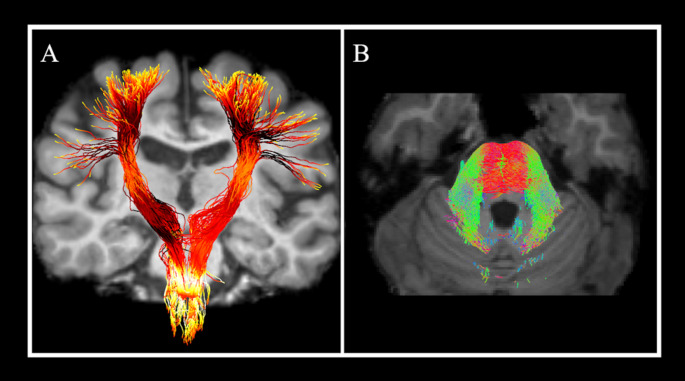

Abstract Image